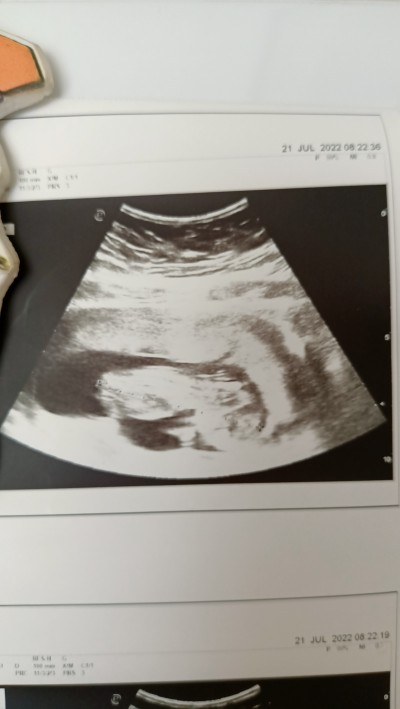

Kızlar 2 gün önce 2li tarama için doktora gittim resim verdi ama bebek yüzüstü gibi duruyor başkalarının bebeklerine bakıyorum hiç böyle görmedim fikri olan yazabilir mi acaba korkulacak bişey var mı 13+2

Gebelik haftası 13+2